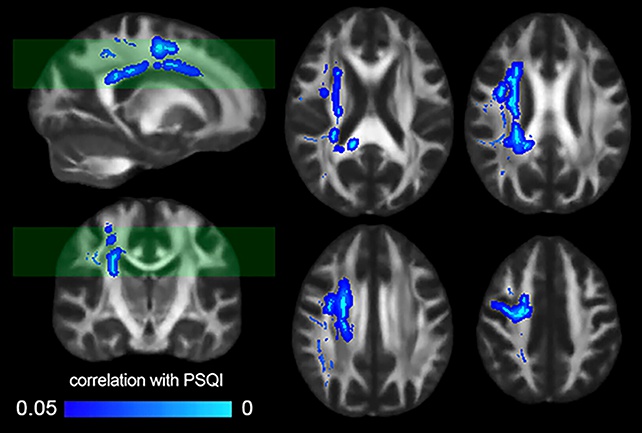

В рамках исследования ученые проанализировали МРТ-сканы 185 здоровых добровольцев. Сопоставление данных визуализации мозга с индексом качества сна PSQI показало: при снижении субъективного качества сна ухудшается передача сигналов в мозге.